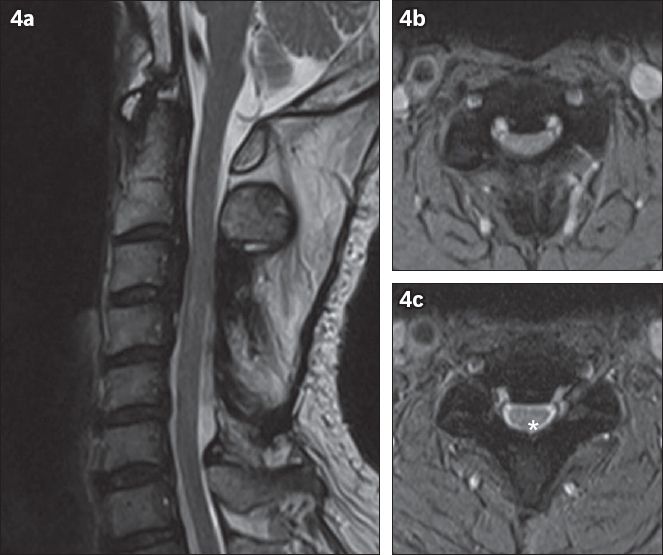

Fig. 6

Top row: classification of ossification of the posterior longitudinal ligament (OPLL) subtypes on lateral cervical radiograph: (a) continuous (arrows show extent of the continuous type); (b) segmental (arrowheads); and (c) mixed (arrows show the continuous type and arrowheads show the segmental type at different levels of the cervical spine). (d) Lateral cervical radiograph shows a normal cervical spine for comparison. Bottom row: OPLL subtypes on sagittal CT multiplanar reconstruction images: (e) continuous; (f) segmental; (g) mixed; and (h) circumscribed. The ‘doublelayer’ sign (arrow) at C2 and C3 vertebral level and the ‘single-layer’ (arrowhead) sign at C4 vertebral level are seen in 6e. Note the small focal circumscribed OPLL (arrow) in 6h.